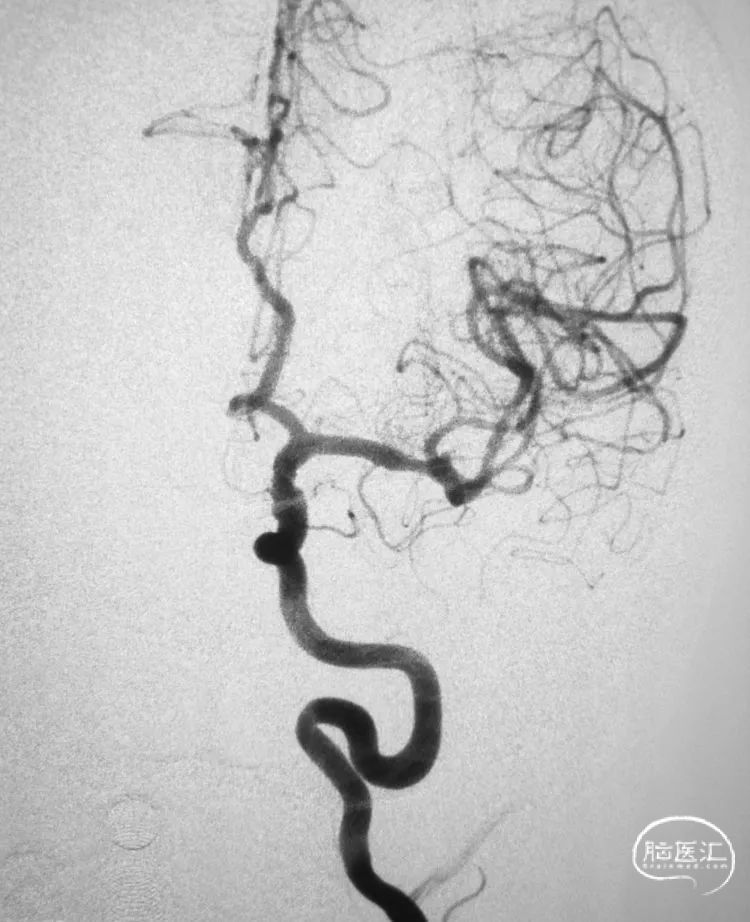

多角度显示动脉瘤,中动脉分三干,瘤体和上干关系密切,宽颈,准备支架!Atlas非常适合这样的血管。